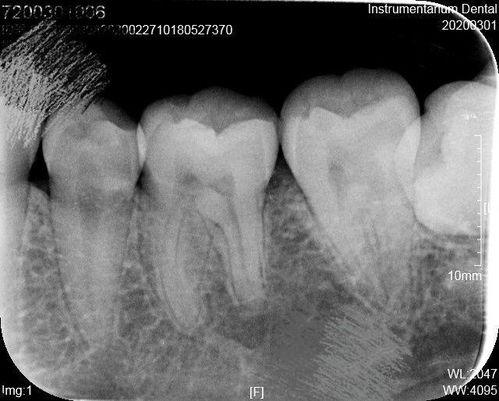

当你意识到智齿可能存在问题时,第一步就是预约口腔专家。专家会通过X光片检查智齿的生长情况,判断是否需要拔除。